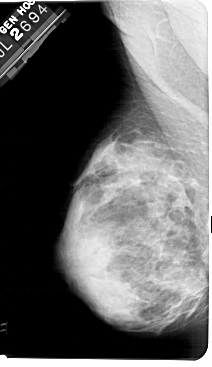

A_1185_1.RIGHT_MLO

LEFT_MLO LINES 5491 PIXELS_PER_LINE 3166 BITS_PER_PIXEL 12 RESOLUTION 43.5 NON_OVERLAY